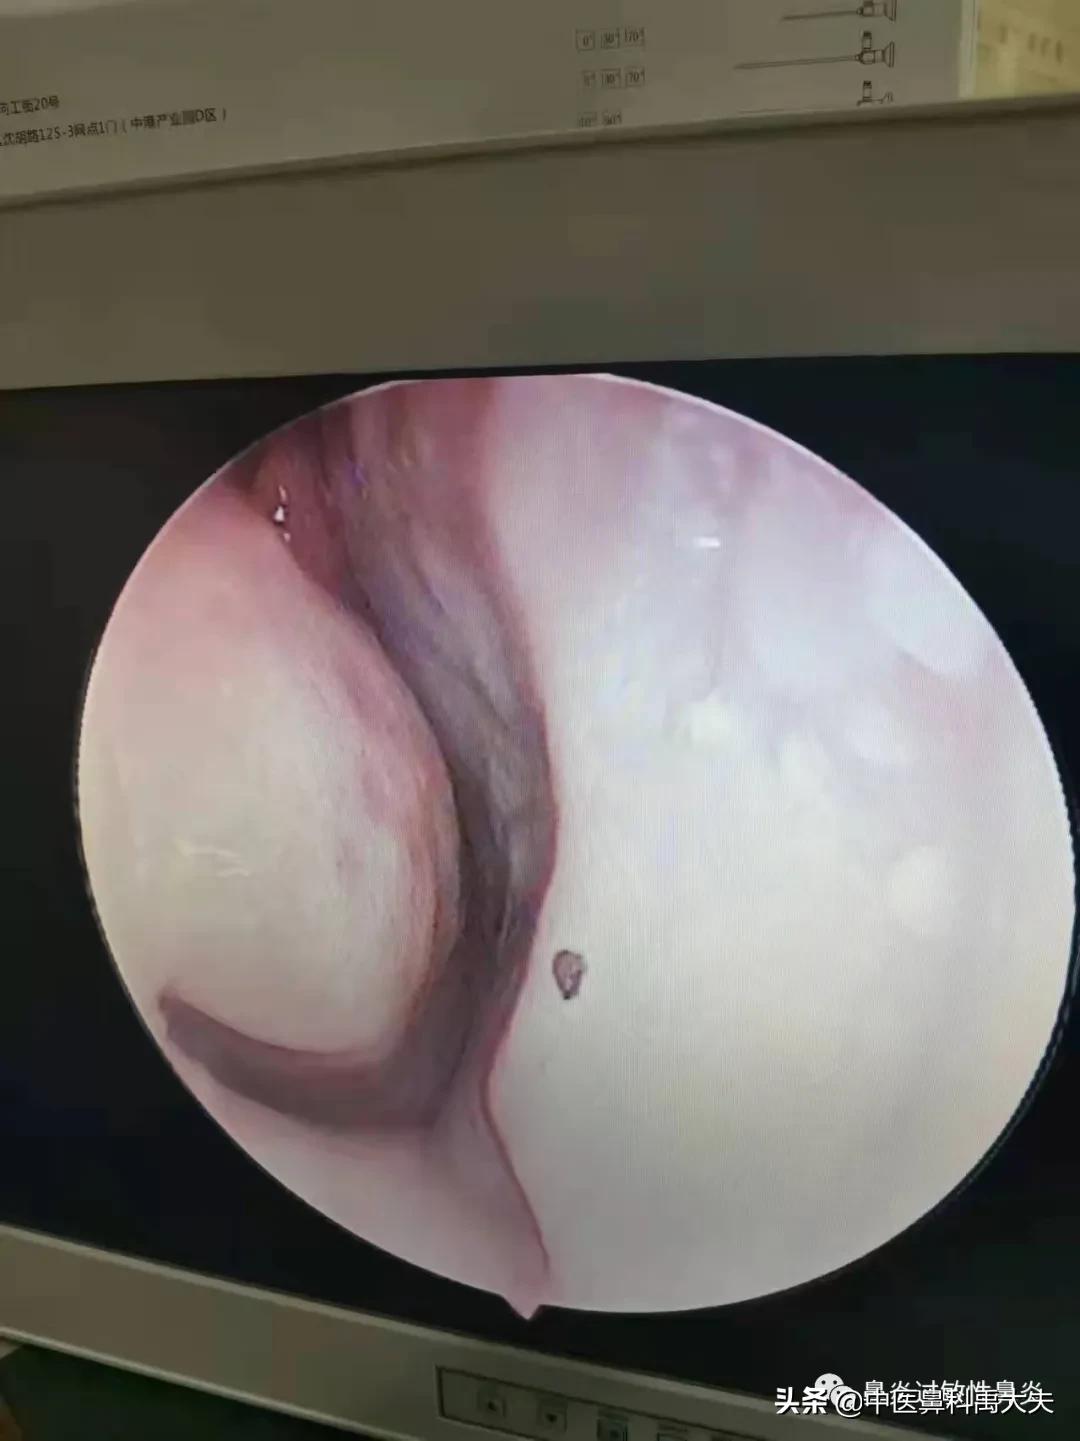

冲洗后左侧鼻腔

冲洗后右侧鼻腔

经过我们的加盟客户一个冲洗护理,大家看看冲洗后的,情况,你就可能已经理解了,整体治疗中,为什么护理占到了三分之一的天下,通过冲洗后的对比,在这里就是呼吁大家对于鼻腔冲洗,我们一定要坚持去做,而且要养成一个良好的习惯。